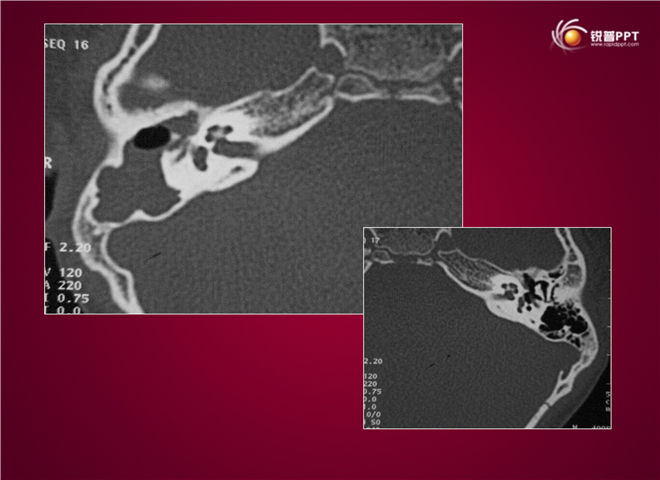

23_CT读片基础